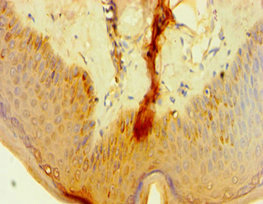

應用范圍:ELISA, IHC

Application Recommended Dilution IHC 1:20-1:200 -